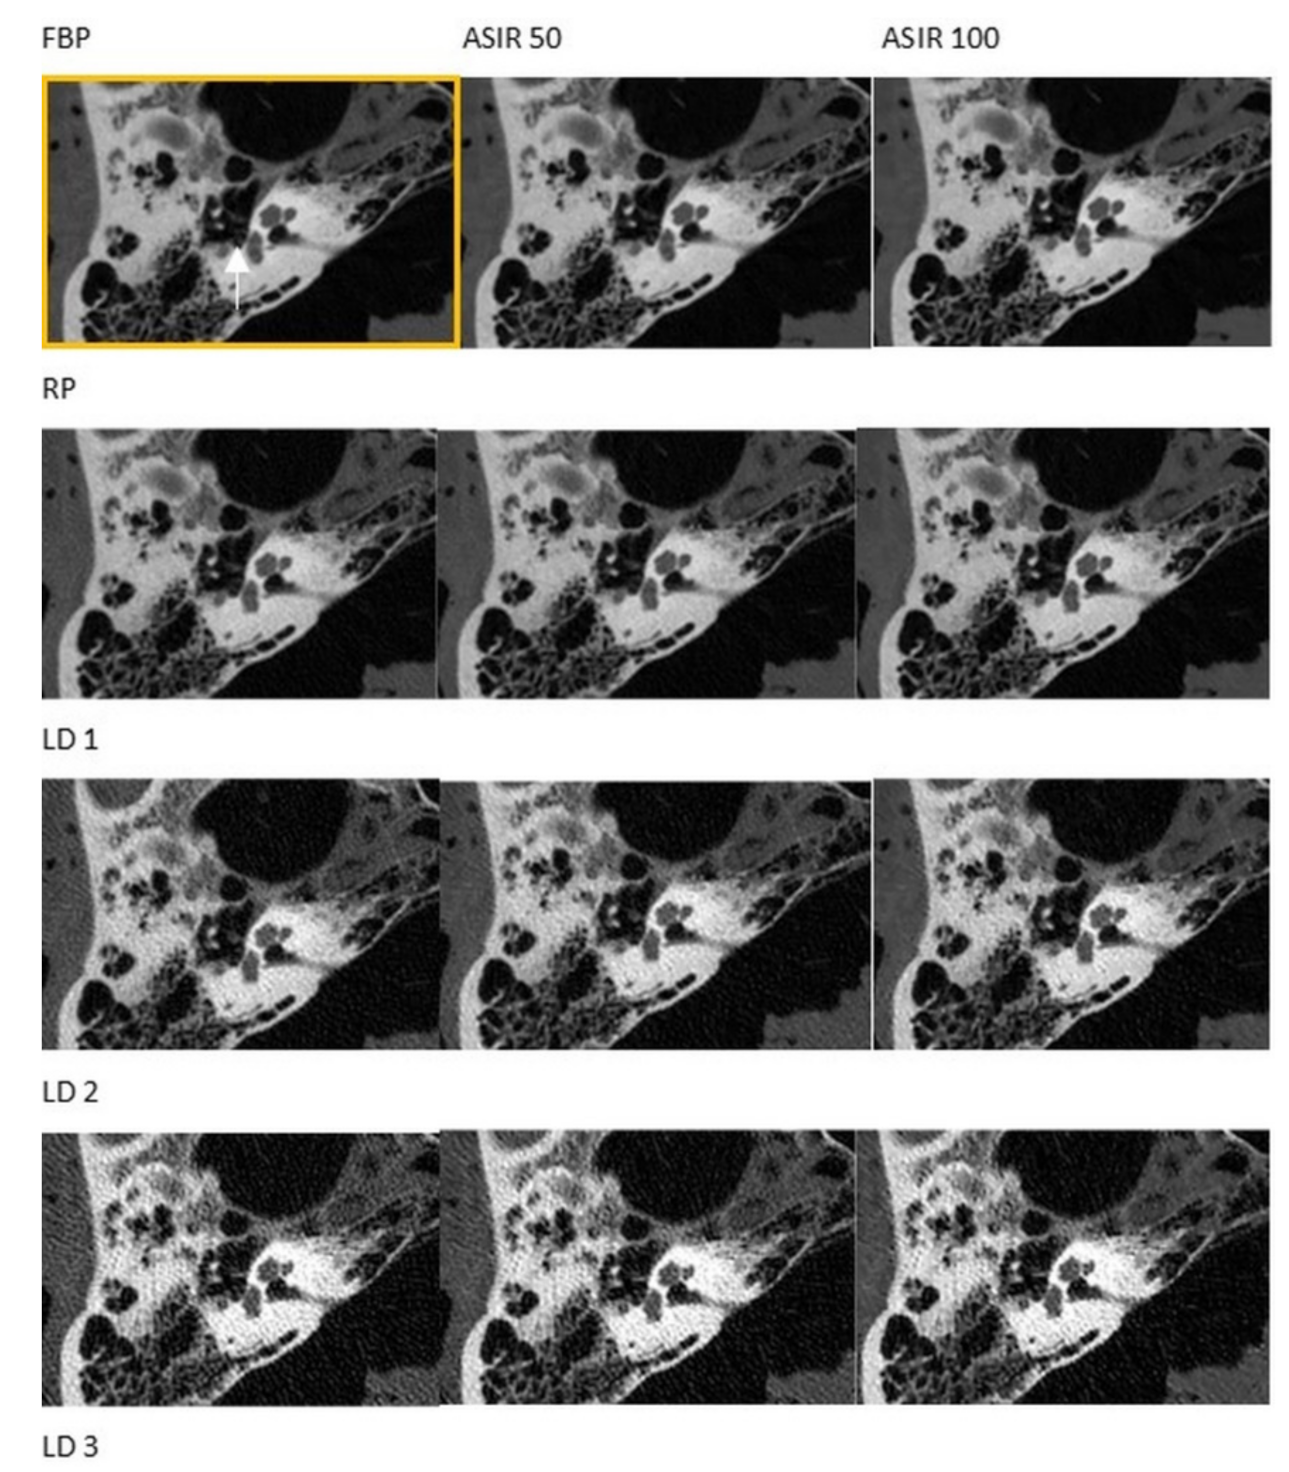

3.1. CT

3.2. CBCT